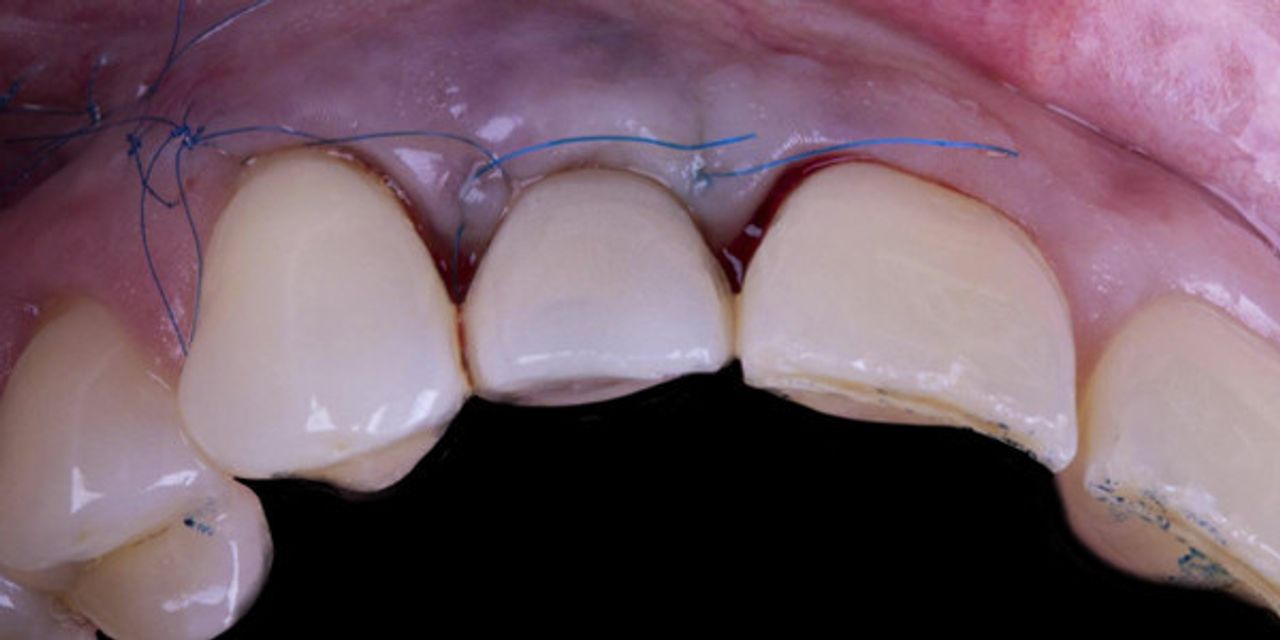

Implant-Perio Evolution 2.0. Surgical Veneer Grafting Protocol: Step-by-Step Utilization in the Esthetic Zone

- Minimally invasive tooth removal techniques and instrumentation- Remove broken and difficult teeth with a flapless approach- The role of socket grafting- Choosing a graft material- Managing the post-extraction sites in order to minimize ridge contour loss- The concept of Restoration-Driven Tissue Regeneration (RDTR)- How to properly place and guide implants into the extraction site for ideal results- How to properly harvest and position in the fresh extraction socket a Connective Tissue Graft